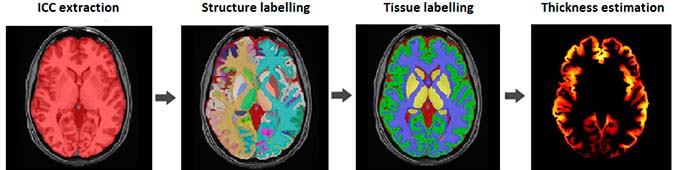

vol2Brain is capable of analyzing up to 135 regions of the brain from magnetic resonance images (MRI), offering information on the volumes of the tissues of the intracranial cavity (ICC) as well as some macroscopic areas such as the cerebral hemispheres, the cerebellum and the brain stem.

Likewise, vol2Brain also provides the volumes and asymmetry indices of cortical and subcortical structures, of great importance in the neurological field, and measurements of cortical thickness. “All this information”, highlights José Vicente Manjón, researcher of the IBIME-ITACA group of the UPV and one of the coordinators of vol2Brain, “is key to advance in the knowledge of neurological diseases”.